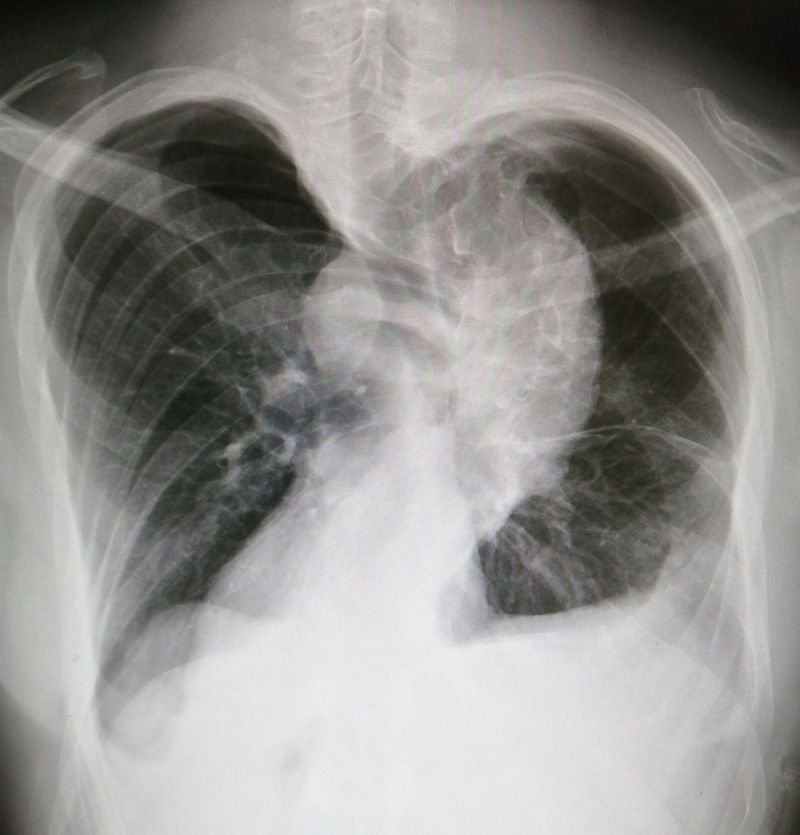

Chest AP View

Structural scoliosis. (A fixed lateral (sideways) with the curve of the spine.)

Xray

Chest

Scoliosis